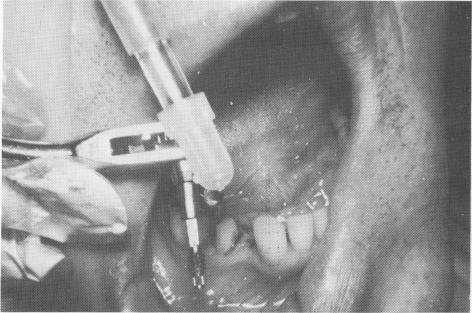

Far more effective than stabilizing with an inlay is splinting the usually stronger distal tooth to the implant with a full crown restoration. The case used as an example is that of a 57-year-old man whose lower right second bicuspid was used as a single abutment for an implant replacement of his first bicuspid. The abutment tooth was prepared for a full crown restoration, and on the next visit a two-unit splint was fabricated, using one of the soft impression materials (Fig. 8-50). (If using copper tube impressions with a modeling compound, this would have been done two visits later.) The splint was tried in the mouth for proper gingival fit, con-tour, and occlusion (Fig. 8-51).

Fig. 8-53. The vent-plant is attached to the ratchet.

1 Splint fitted into position prior to single tooth implant insertion

4 Mandibular vent-plant implant attached to the ratchet